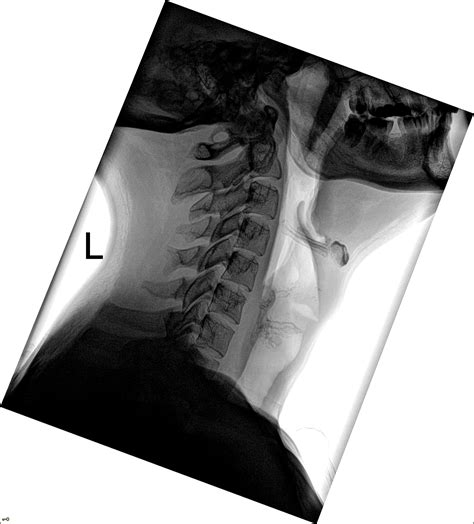

A Soft Tissue Neck Xray is a medical imaging technique that uses low-dose X-rays to produce images of the soft tissues in the neck region. Unlike traditional X-rays that focus on bones, a soft tissue X-ray is designed to visualize structures such as muscles, tendons, and ligaments. This makes it an invaluable tool for diagnosing conditions that do not involve bone abnormalities.

• The patient is positioned comfortably on an X-ray table, usually lying on their back or sitting upright.

• The radiologist or technician will position the X-ray machine to capture images of the neck from different angles.

• soft tissue neck xray positioning

• soft tissue neck xray position